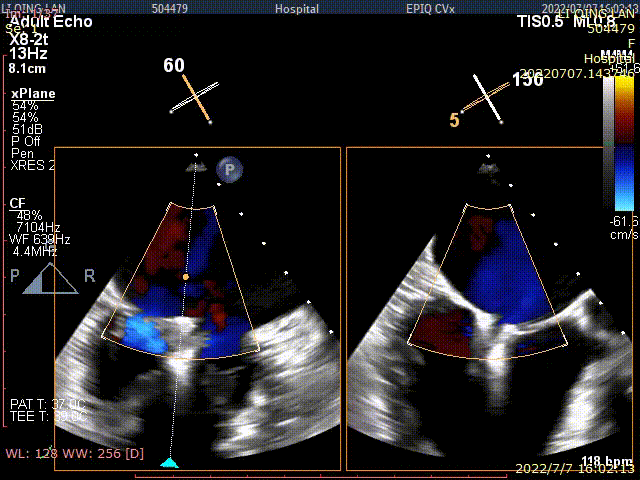

术后TEE显示,二尖瓣双孔化形成,反流明显减少